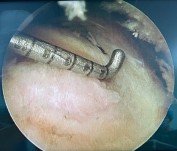

Đóng neo khâu theo, tiến hành tạo vi tổn thương tại diện bám CX qua nội soi theo kỹ thuật kỹ thuật phối hợp của nhóm tác giả Stephen J. Snyder và nhóm tác giả Guiseppe Milano, áp dụng một số đặc điểm nghiên cứu về KC giữa bờ ngoài diện bám và bờ sụn khớp để tính toán vị trí tạo vi tổn thương24,25:

- Sử dụng dùi nội soi đường kính khoảng 1,6mm, dùi này được đưa vào qua cổng vào thích hợp và được đặt vuông góc với vỏ xương cứng sau đấy đâm thủng và đi vào xương xốp. Tạo các lỗ vi tổn thương ở phía trong vị trí đặt neo, các lỗ này được đóng sâu khoảng 5mm hoặc đến khi nào thấy các giọt mỡ thoát ra là được.

- Dựa vào các chỉ số KC từ bờ ngoài diện bám gân CX mà cụ thể là từ điểm bờ trước ngoài gân trên gai, dưới gai, tròn bé đến bờ sụn khớp(từ 10,01 - 10,25- 12,8mm) so với bề mặt sụn khớp để tính toán vị trí tạo vi tổn thương sao cho KC giữa các lỗ khoảng từ 4-5 mm trở lên và không có quá một lỗ giữa hai neo chỉ sát nhau (trong trường hợp khâu từ 2 neo trở lên) để tránh nguy cơ yếu neo chỉ. Chúng tôi thường tạo vi tổn thương theo 2 hàng với vị trí hàng tạo vi tổn thương đầu tiên sát rìa sụn khớp, hàng thứ 2 tiếp theo vị trí ở phía ngoài so với hàng thứ nhất 5mm và vị trí các lỗ vi tổn thương đan xen với hàng đầu tiên.

Hình 2.22. Hình minh hoạ cách tạo lỗ vi tổn thương theo hàng phía trong vị trí đặt neo

- Để thuận tiện cho quá trình tạo vi tổn thương chúng tôi tạo dụng cụ dùng để tạo vi tổn thương có cấu tạo giồng kiểu compa. Dụng cụ này gồm 1 phần cố định (chân compa) hàn gắn cố định với 1 ống rỗng có lòng đường